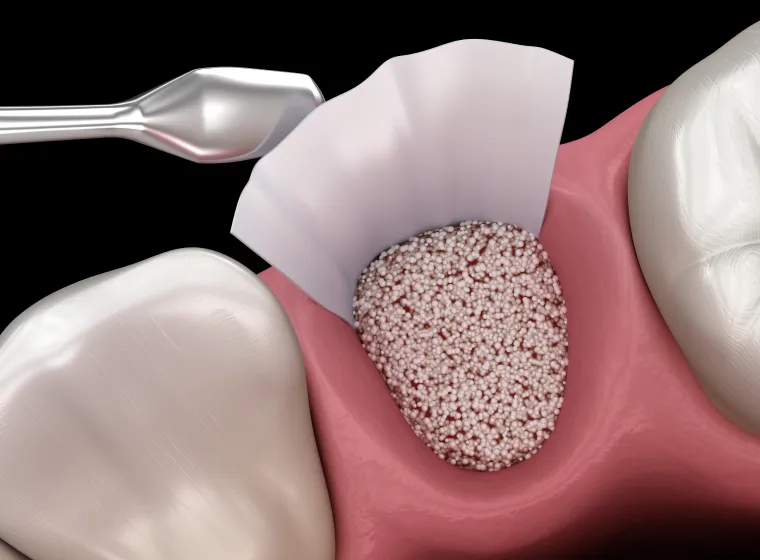

GBR法(骨誘導再生法)

骨の不足した部位に人工骨や自家骨を補填し、特殊な膜で覆って骨の再生を促す方法です。部分的な骨欠損に適しており、インプラント埋入と同時に行える場合もあります。

このほか、ソケットリフトやスプリットクレストなど、患者様ごとの状態に適した方法を選択します。骨造成は「骨が足りないからインプラントはできない」と言われた方にとって、新たな選択肢をもたらす技術です。

一方で、重度の歯周病や根の破折などにより保存が難しい歯は、**抜歯と同時にインプラントを埋入する“抜歯即時インプラント”**を選択できる場合があります。これにより、骨や歯ぐきの退縮を防ぎつつ治療期間を短縮できるのが特徴です。